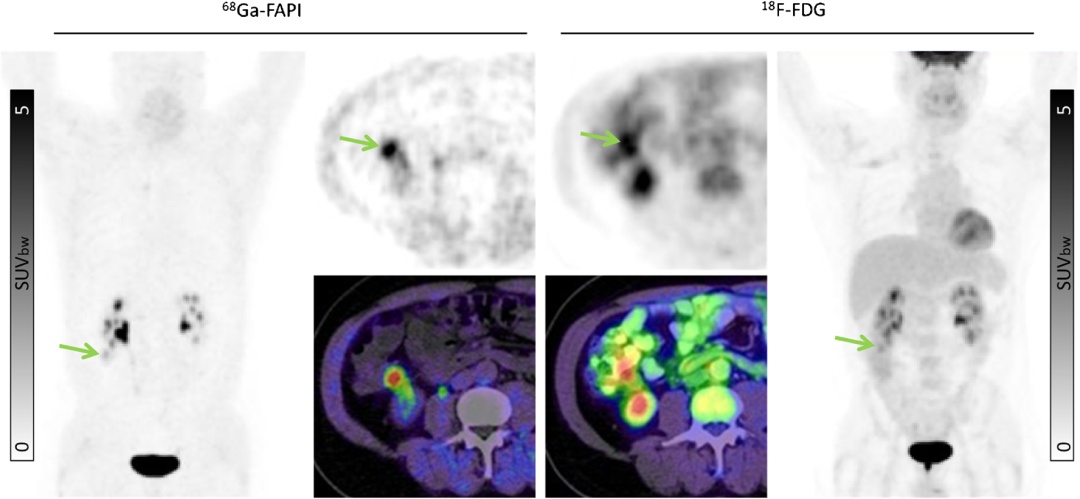

与FDG PET显像不同的是,FAPI PET显像不依赖于血糖水平,因此不需要控糖、禁食4-6小时的准备。且在许多正常组织如脑、肝脏、肾、胃肠道、口鼻粘膜、心肌中的生理性摄取低于FDG,为病灶的显示提供了更干净、清晰的组织背景(图3、图4)。

图3 肠道炎性改变导致FDG摄取增加(右图),但FAPI显像未见肠道明显摄取,提高诊断能力[2]

图4 55岁男性确诊为右半结肠癌(升结肠)行PET/CT显像术前分期,FAPI和FDG均显示出高代谢征象(绿色箭头),FAPI SUVmax=6.25;FDG SUVmax=5.34,FDG图像中肠道背景影响真正癌灶的显示和判断[2]

另外,许多FDG PET影像上呈 “中等度摄取”或“高本底”的肿瘤,FAPI能够很好的避免这些问题,提供差异化的成像对比。如:①提升中高分化肝细胞肝癌、胆管细胞癌的显示能力;②对前列腺癌(尤其PSMA阴性者)、肾透明细胞癌提供重要影像补充;③神经内分泌肿瘤(NET)、肉瘤:为部分低级别G1/G2级 NET及软组织肉瘤提供更清晰的肿瘤边界与负荷评估;④消化道腺癌,部分粘液或印戒细胞癌可能显示出更高的摄取值(图5)。